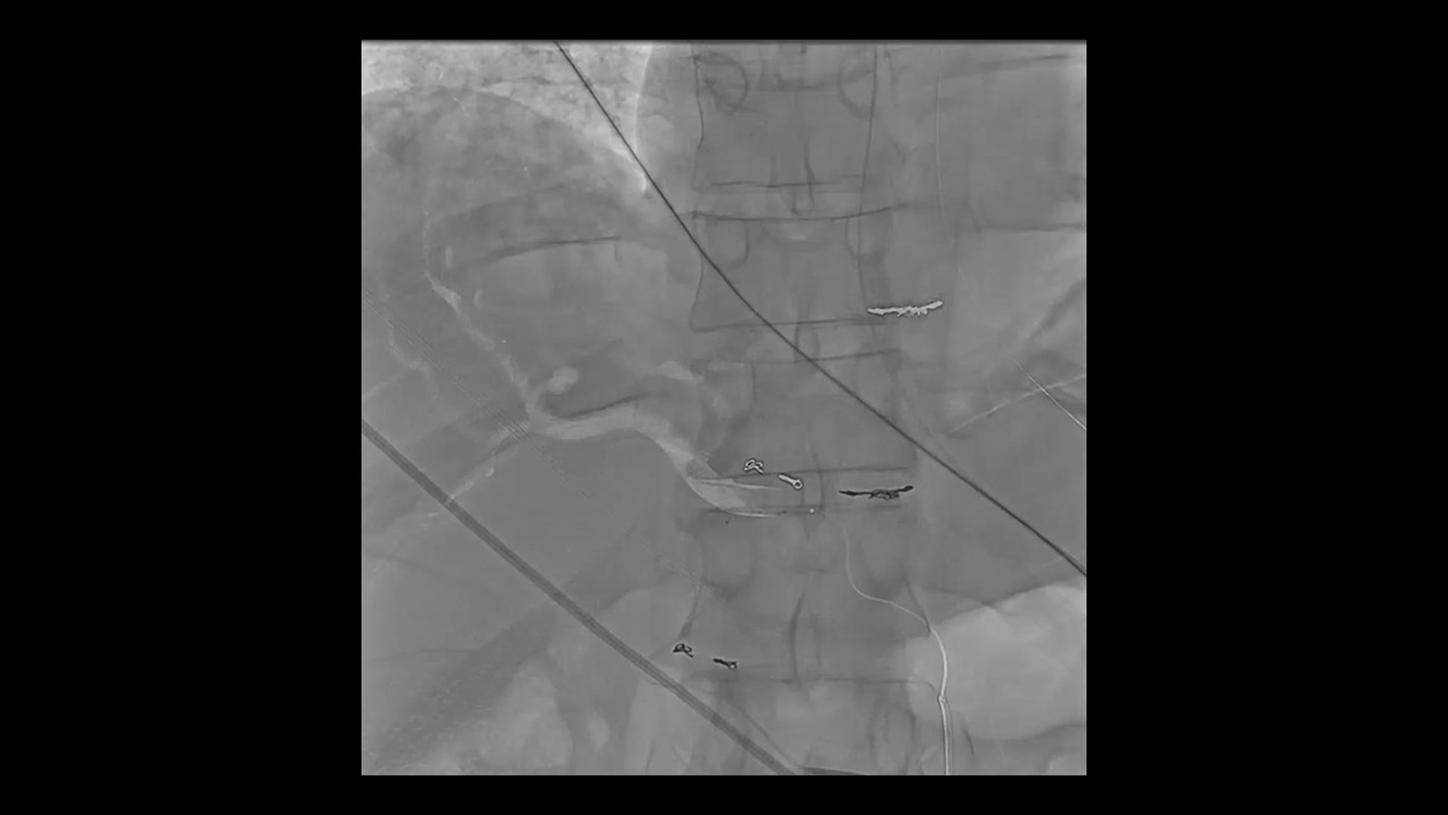

During minimally invasive procedures, it is critical to have a clear view of anatomies and devices. Yet complex imaging tasks or challenging patient conditions often impact image quality. OPTIQ AI delivers constant image quality1 defined by CNR in support of the ALARA principle, independent of patient or C-arm angulation. On top, an AI-powered algorithm reduces image noise in real time across different 2D imaging modes.

Make AI-powered imaging and clear insights your standard during interventions – with OPTIQ AI.